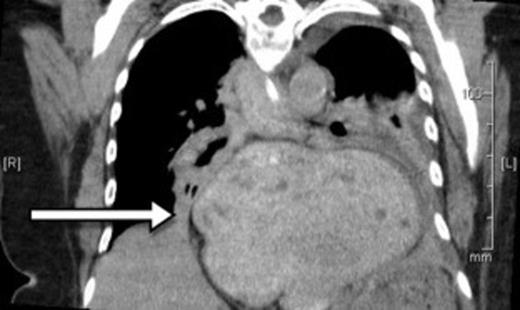

A 73-year-old Caucasian woman presented to the emergency department with 2-day history of vomiting and vague abdominal pain. Her background history included asymptomatic hiatus hernia, morbid obesity (BMI of 35.7), polymyalgia rheumatica, previous laparoscopic cholecystectomy, hypercholesterolaemia and hypertension. Regular medications included prednisone, amlodipine and cilazapril. On presentation she was tachycardic at 110 beats/min with otherwise normal vital signs. Her abdomen was generally tender but without any localised peritonism. Initial laboratory investigations on admission showed a leukocytosis (WCC of 13.8 x 109/L). Routine X-ray (figure 1) and subsequent (CT) scan (figure 2) both revealed a large strangulated paraoesophageal hernia. Radiographic changes (figure 3) were seen with gas within stomach wall, suggestive of gastric necrosis.

CT showing a large strangulated paraoesophageal hernia (arrow) within the thoracic cavity